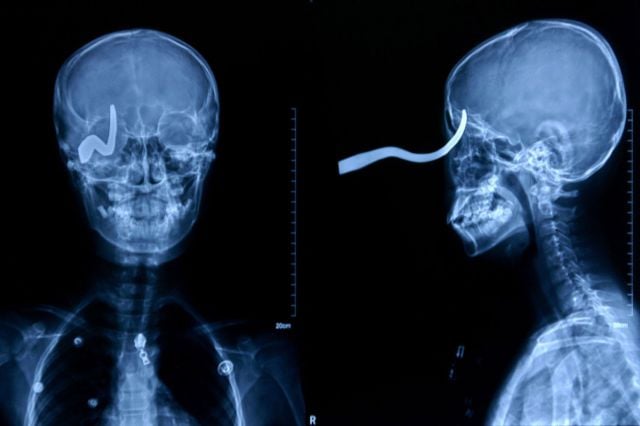

Eleven-year-old Chinese schoolboy Liu Cheong had a brush with death when his friend shot him in the head with a 16-inch arrow, according to numerous international media reports. The arrow entered his skull through the eye socket and lodged in the back of his head. Somehow, the boy was spared a fatal brain injury.

The 5-centimeter nail shown in this X-ray was found after a man came to a Seoul, South Korea, hospital complaining of a severe headache. After examining and interviewing the man, doctors speculated that the nail had been the result of an accident four years before his visit, but that the man did not know the nail was lodged in his head.